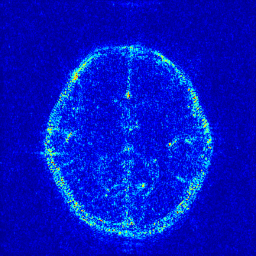

We evaluate the proposed DECN framework using PSNR and SSIM (structural similarity index) [30] as quantitative image quality assessment measures. We give the quantitative reconstruction results of all the test data on different under-sampling patterns and different under-sampling ratios in Table II. We show the Cartesian 30%percent3030\% under-sampling mask in Figure 6(b) and the Random 20%percent2020\% under-sampling mask in Figure 7(b). We observe that DECN improved all off-the-shelf CS-MRI inversion methods on all the under-sampling patterns. Since the Random mask enjoys the more incoherence than the Cartesian mask with the same under-sampling ratio, the CS-MRI achieves better reconstruction quality on the Random masks. Also, we observe the plain DC-CNN model already achieves good reconstruction accuracy, leaving less structural errors for the error correction module, leading to the limited performance improvement about 0.1 dB on the Random 20%percent2020\% and 30%percent3030\% masks. While for other CS-MRI inversions on various sampling patterns, the improvements are at least 1.5dB or even up to 3.5 dB.

In Figure 6, we show reconstruction results and the corresponding error images of an example from the test data on the 1D 30%percent3030\% under-sampling mask. With local magnification on the red box, we observe that by learning the error correction module, the fine details, especially the low-contrast structures are better preserved, leading to a better reconstruction.

In Figure 7, we also compare the MR images produced by the TLMRI, PANO and GBRWT with their DECN counterparts on the 2D 20%percent2020\% under-sampling mask. The subjective comparison DC-CNN and DE-CNN-DECN isn’t included because of the limited improvement. The results are consistent with our observation in Cartesian under-sampling case.